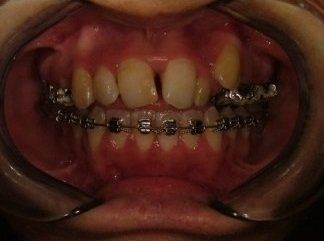

Il trattamento ortodontico non è solo per i bambini: se hai denti storti, affollati, mancanti o prominenti che ti impediscono di masticare e parlare liberamente, potrebbe essere necessario rivolgersi a uno specialista. L’ortodonzia prevede l'uso di apparecchi ortodontici, che possono essere fissi o rimovibili.

I dentisti studiano infatti le anomalie di costituzione, posizione e sviluppo di denti e ossa mascellari, e progettano l’apparecchio mirando al ripristino della corretta funzionalità dell'apparato masticatorio.

L’ortodonzia non dimentica neanche l’importanza dell’estetica e la sicurezza che un bel sorriso può portare. Per questo un apparecchio può avere come obiettivo anche quello di riportare il profilo facciale nella posizione più corretta possibile e di restituire al paziente un aspetto migliore, oltre che la fiducia in se stesso.